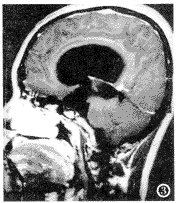

11例脑积水中,10例为中脑导水管以上梗阻性脑积水,1例交通性脑积水。由于脑积水使第三脑室前份扩大压迫视交叉,其中6例视交叉受压前上抬,5例视交叉受压向前移位(图3)。

图3 脑积水,扩大的第三脑室前部压迫视交叉。